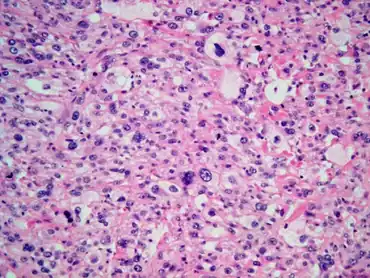

| Malignant fibrous histiocytoma of urinary bladder as a post-radiation secondary cancer-Highly pleomorphic neoplastic cells with clear eosinophilic cytoplasm | |